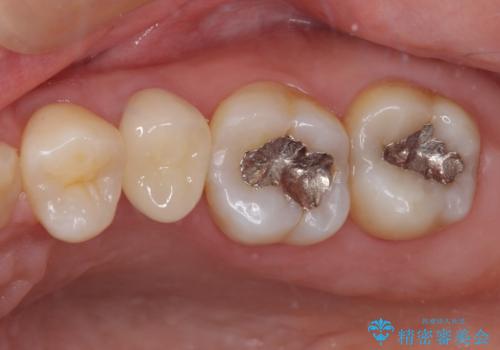

- 近医にてむし歯治療を行った後に痛みが出たとのことで来院された患者様です。

左下奥歯は術後から咬合時の痛みが発現し、来院時には脈を打つような痛みが認められました。

診察の結果、神経を取り除く必要があると判断されたため根管治療を行いました。

その後、左上の奥歯にも咬合時の痛みが認められ、レントゲン写真より歯内の神経が失活していることが分かりました。

2歯ともに根管治療を行い、その後はオールセラミッククラウンにて補綴治療を行うこととしました。